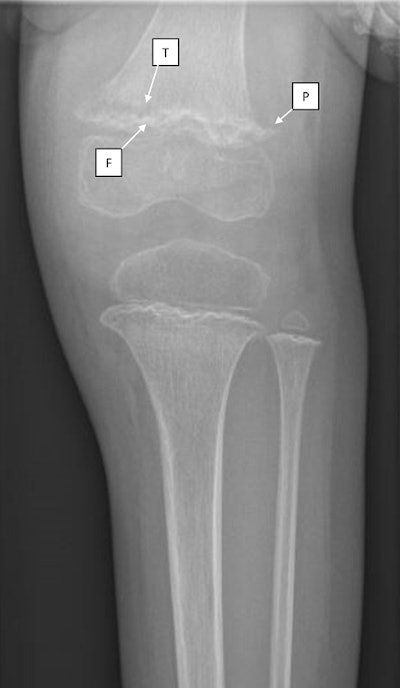

Subsequent images of the girl's distal femur and proximal tibia showed three common radiological findings in scurvy:

- Frankel lines -- dense zones of provisional calcification

- Pelkan spurs -- bony spurring at the periphery of the zone of metaphyseal calcification

- Trümmerfeld zone -- lucent bands in the metaphysis below the Frankel line

"These radiographic findings, in conjunction with the clinical findings of mucosal bleeding, perifollicular petechiae, and arthralgias, suggested a diagnosis of scurvy," wrote first author Dr. Matthew Wiese, a pediatric emergency medicine fellow at Oishei Children's Hospital.